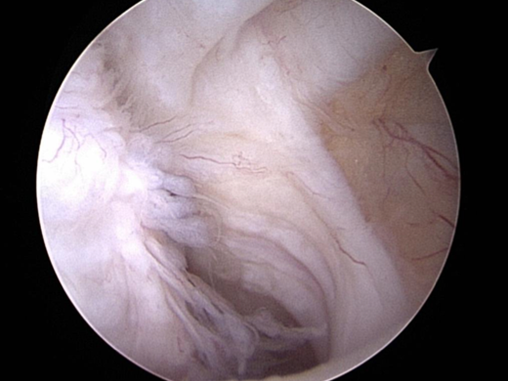

Once this is done we would then talk about the results and findings and decide upon the next step, in some cases we can make a diagnosis and start a conservative treatment straight away (such as a minor medial ligament injury) in other cases we may need to image structures inside the joint by arthroscopy and in other cases we may elect to consider arthroscopy for diagnosis and also perform a surgical procedure (reconstruction of a traumatic ligament injury, debridement of a biceps tendon impingement, removal of a fragmented caudal glenoid).

- Acute ligament injuries and instabilities to the shoulder will usually be treated by ligament repair and support. This may have to be done as an open procedure or we may be able to perform this arthroscopically at the same time as making the diagnosis, a good example of this would be a traumatic medial glenohumeral ligament tear treated by arthroscopically guided “Tightrope”.

- Ligaments may also be injured through repetitive strain and treating these in a less invasive way may help. Medial Shoulder Instability syndrome is such an example. Injury to the Lateral Glenohumeral Ligament however often does require reconstruction which is typically done arthroscopically.

- Caudal shoulder instability syndrome is a condition that we are just starting to appreciate. The shoulder is a joint that will often tolerate considerable injury and when the cause of that injury is a repetitive strain little on little build up occurs over time. In this condition which we have recognised and we are starting to build up a better understanding of, damage to one or more of the supporting structures but primarily the biceps tendon leads to a front to back micro instability. This in turn leads to the humeral head impacting onto the caudal glenoid rim and eventually a fragment breaks off in this site. Removal of the fragment can sometimes help but there is often considerable damage already inside the shoulder with full thickness loss of cartilage. In these cases vigorous physiotherapy, shoulder support braces, oral pain killers and biologic treatments are used to try and improve things however the prognosis may not be good and this does seem to depend heavily on the extent of cartilage loss